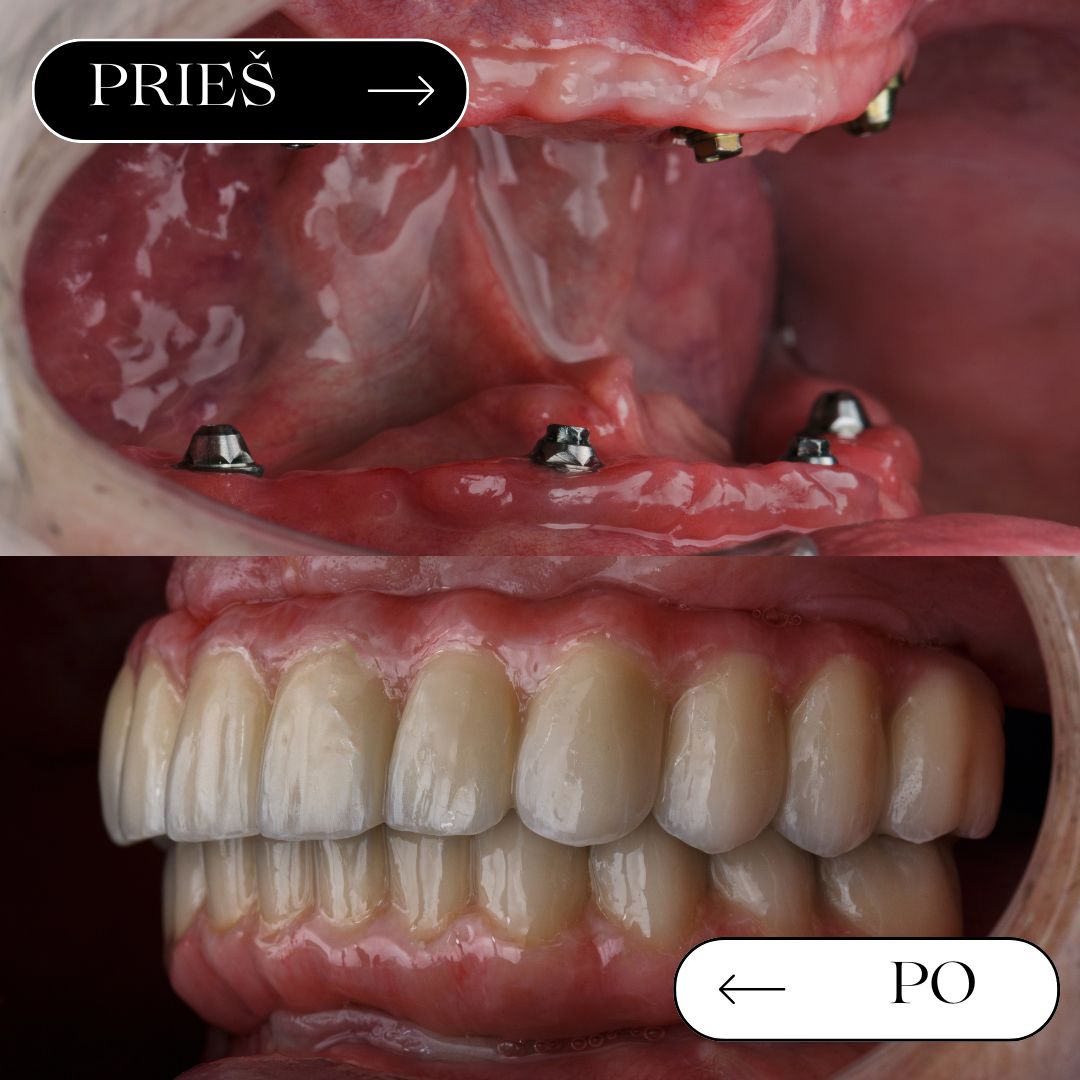

Prieš / po

rezultatai

Geriausias įrodymas – realūs pacientų pokyčiai. Atkurta estetika ir funkcija gali leisti vėl šypsotis be baimės.

Pilnas žandikaulio atkūrimas